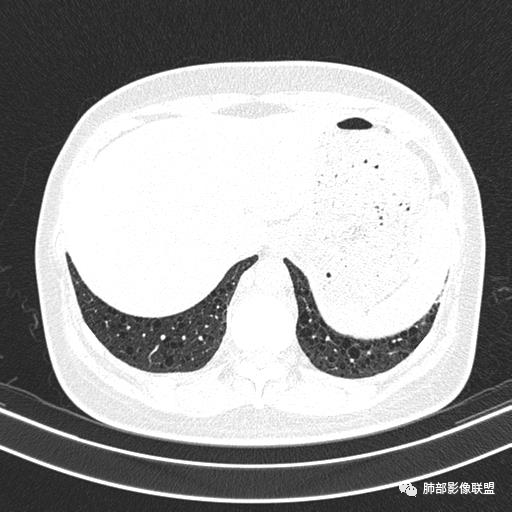

双肺弥漫囊腔,累及肋膈角,囊腔形态相对规则单一。

女,46,活动性气喘1年。苯吸入史半年。胸部CT:两肺弥漫囊腔,上至肺尖,下至肋膈角,形态类似小囊腔。考虑:LAM,鉴别LIP,BHD,PLCH等。

双肺弥漫大小不一薄壁含气囊腔,囊间肺组织正常,正常肺背景,肺尖肺底受累;青年女性,气喘,支持LAM

CT表现:双肺弥漫大小不等的薄壁囊腔,囊壁<2mm,外形规则,血管影多位于囊腔周围,囊腔之间肺组织正常,随着疾病进展到晚期,囊腔变大、增多,不可胜数,囊腔可融合成较大的囊,与肺气肿相似,形成间质性肺纤维化。部分病例可出现结节影。